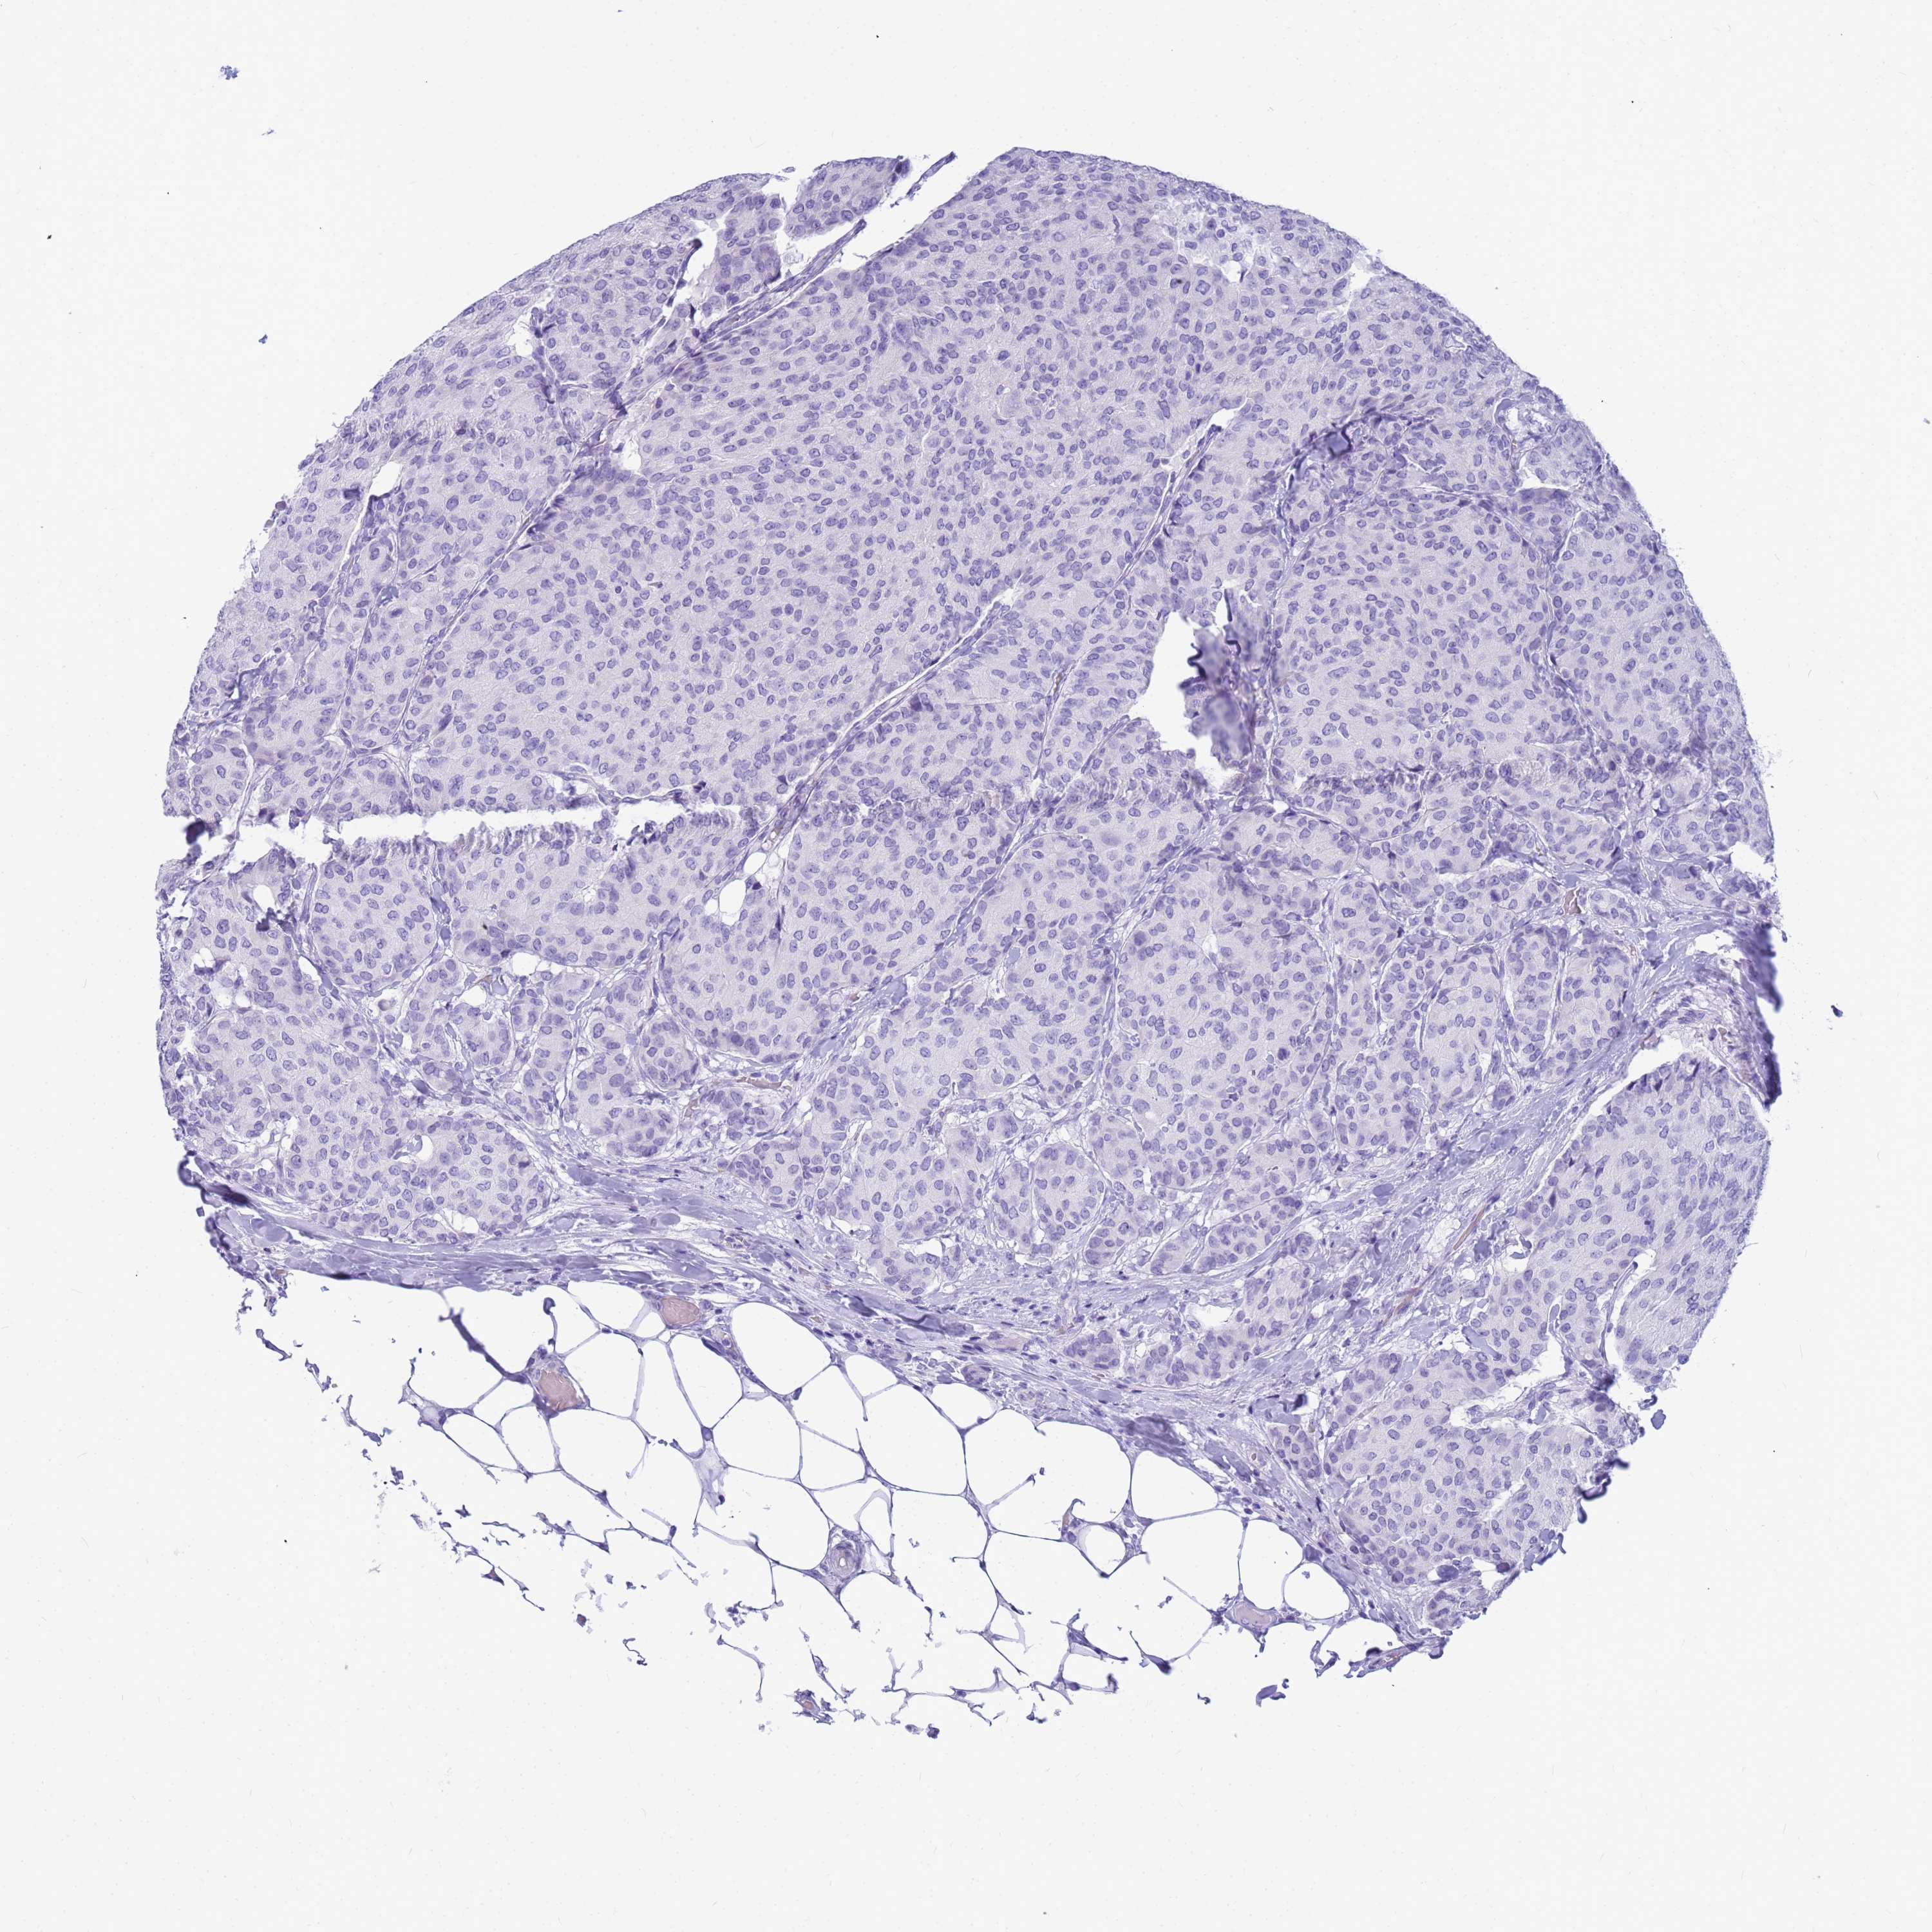

CANCER BREAST CANCER Show tissue menu

BRCA TCGA BRCA VALIDATION PROTEIN EXPRESSION